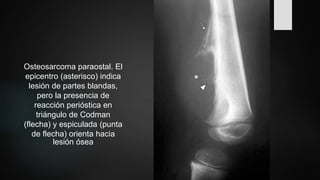

Radiologia Brasileira - Osteossarcoma parosteal: aspectos na radiologia convencional